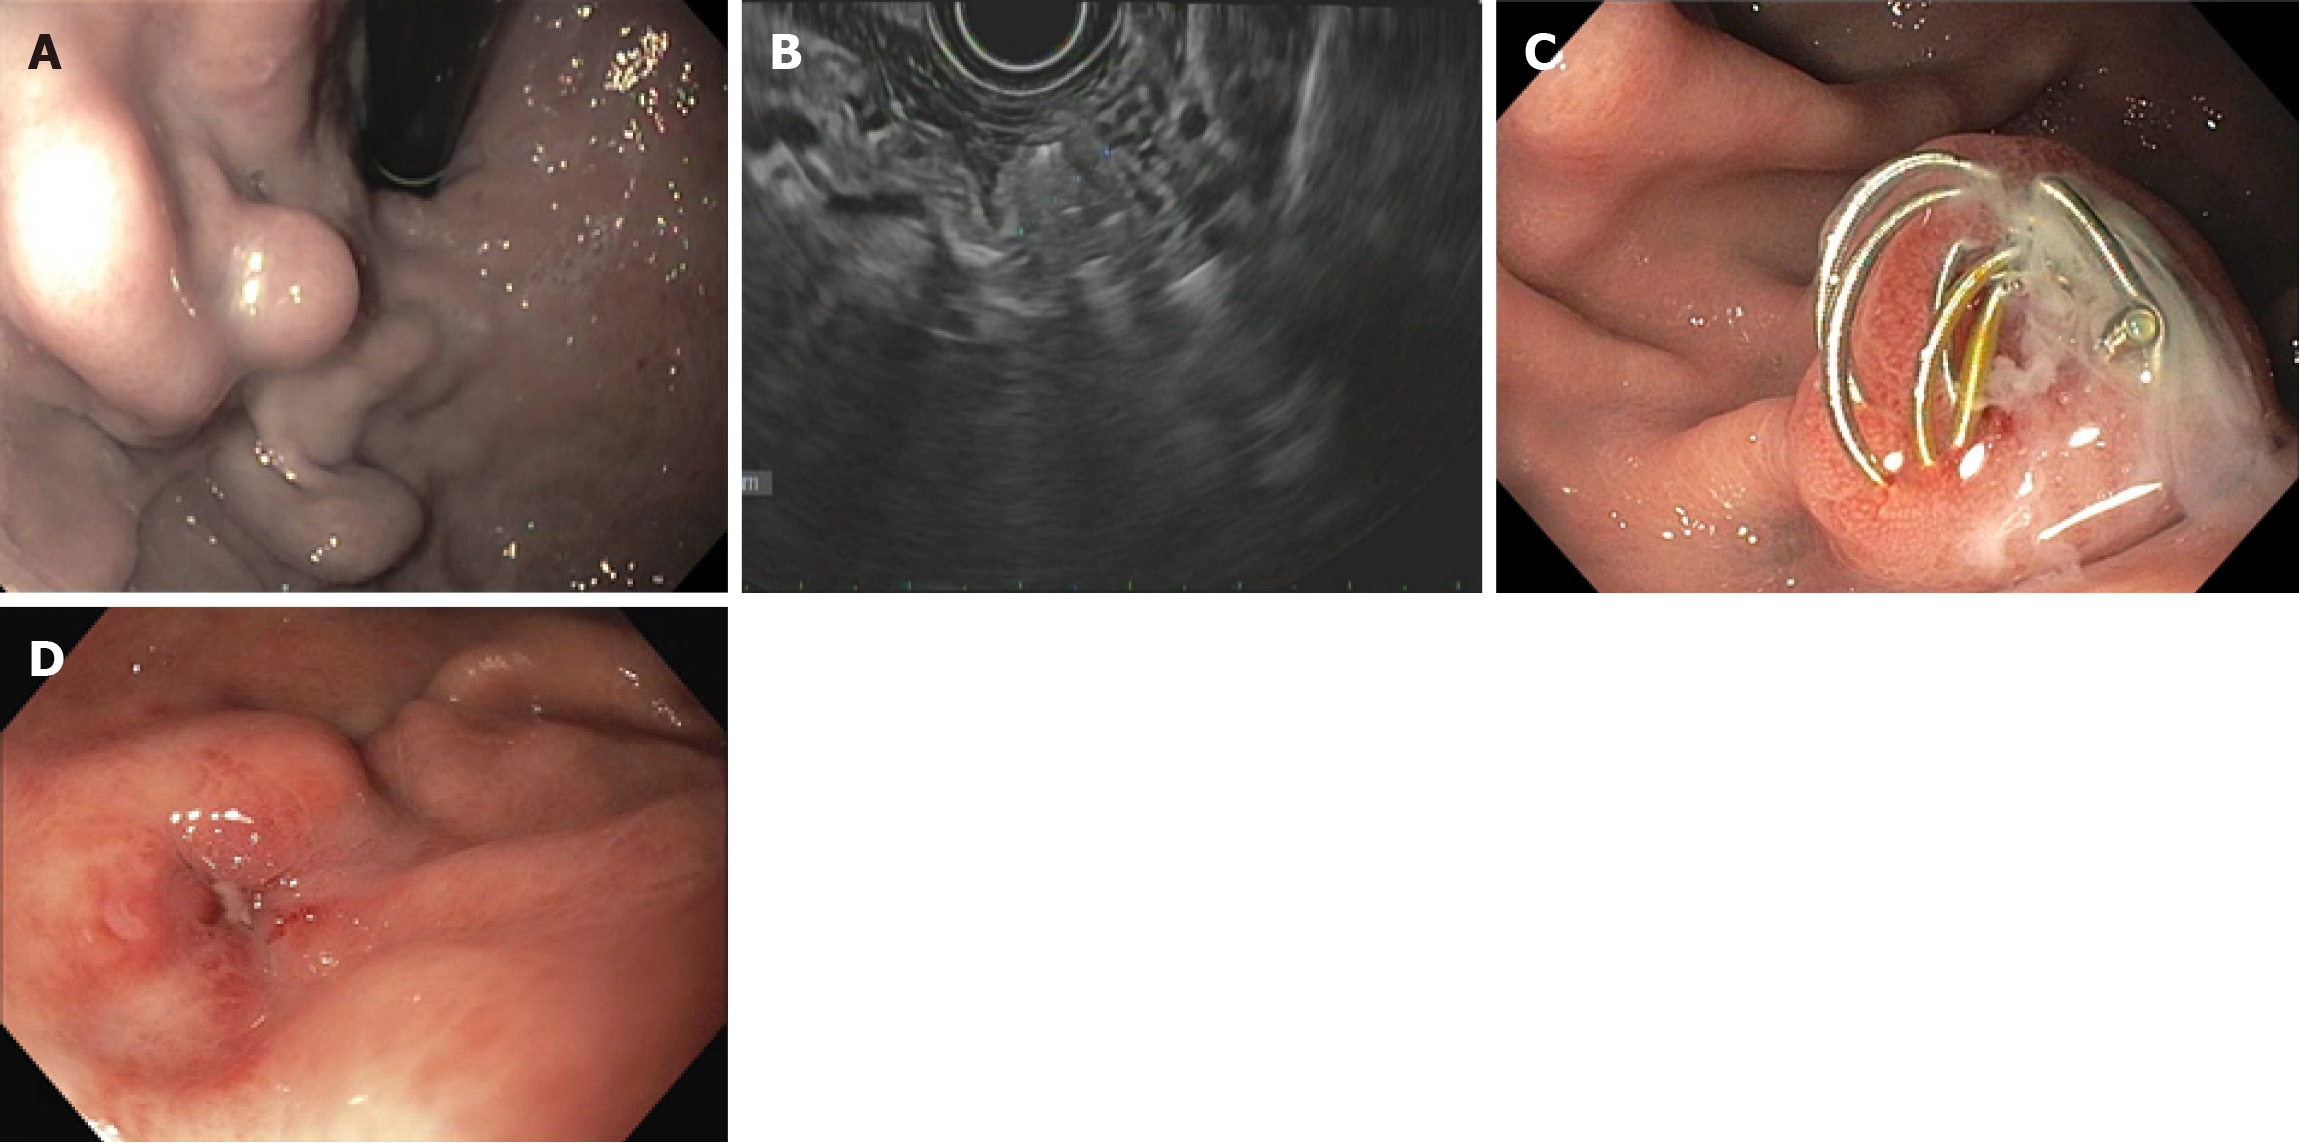

Figure 3

Figure 3 24-year-old male with history of portal vein thrombosis and hepatic encephalopathy was recently hospitalized with hematemesis and found to have gastric varices on upper endoscopy. Imaging showed no evidence of gastro-renal shunt. He was referred for endoscopic ultrasound (EUS) guided therapy of gastric varices. A: Upper endoscopy showing isolated gastric varices type 1; B: EUS showing complete thrombosis of varices following EUS guided coil embolization and cyanoacrylate glue injection; C: Coil extrusion on follow-up endoscopy at 3 months; D: Follow-up endoscopy at 1 year showing complete eradication of varices.